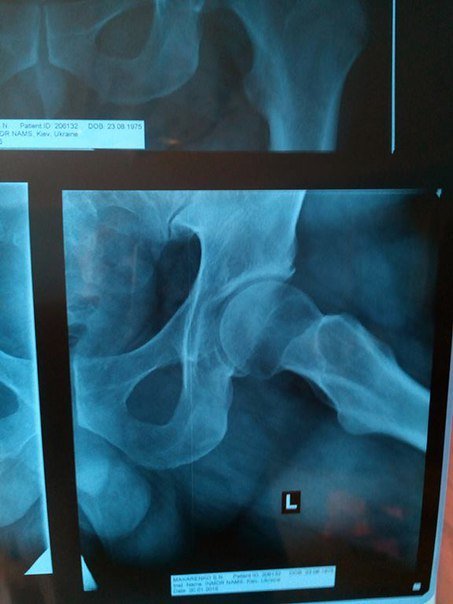

Сергію Макаренко потребує заміни тазобедренного суглоба правої ноги. Операцію робитимуть у Шведсько-українському медичному центрі в Чернівцях. Операція, якісний керамічний протез та двотижнева реабілітація коштують 7500 доларів США.

«З огляду на те, що я маю невеликі доходи у сфері своєї діяльності і значну частину їх з’їдає винаймання житла, сплата комунальних послуг та утримання сім’ї, то вказану суму я буду збирати дуже довго і за цей час я можу взагалі опинитися у інвалідному візку.Багатої та забезпеченої рідні я теж не маю, тож вимушений звертатися до вас друзі. Буду вдячний за будь яку допомогу. Якщо у Вас є контакти, куди можна звернутися по допомогу, теж буду дуже вдячний. Обіцяю документально відзвітувати, якщо вдасться зібрати необхідну суму та зробити операцію, і звітувати кожного тижня про грошові надходження на рахунок. Також додаю рентгенологічні знімки та висновок. Можете порівняти як виглядає мій відносно здоровий суглоб з тим який треба протезувати. Знімок R, це той який потрібно протезувати», – пише на своїй сторінці у мережі Сергій Макаренко.